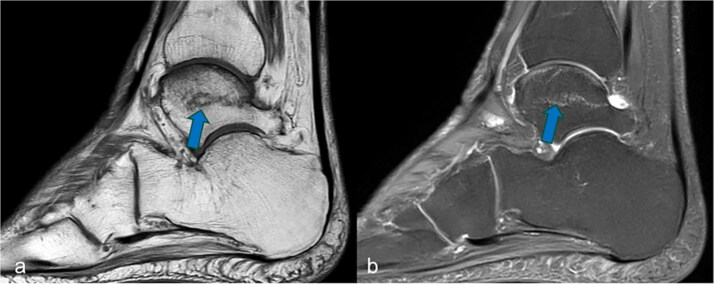

不全性骨折是众所周知的炎症性风湿病患者并发症,但也可由长期甲氨蝶呤(MTX)治疗引起。我们报告了一位72岁的女性患者,患有类风湿关节炎,并接受了超过10年的甲氨蝶呤治疗,她被诊断为滑车不全骨折,以前没有外伤。在停止MTX治疗并开始骨合成代谢治疗后,有明显的临床改善,骨折迅速愈合。该病例强调了早期MRI诊断和治疗调整对疑似MTX骨病病例的重要性,以避免遗漏或延迟骨折愈合,并尽量减少进一步骨折的风险。

Insufficiency fractures are a well-known complication in patients with inflammatory rheumatic diseases, but can also be caused by long-term methotrexate (MTX) therapy. We report on a 72-year-old female patient with rheumatoid arthritis and more than 10 years of MTX treatment who was diagnosed with an insufficiency fracture of the trochlea tali without previous trauma. After discontinuation of MTX therapy and initiation of osteoanabolic treatment, there was a distinct clinical improvement with prompt fracture healing. The case underlines the importance of early MRI diagnosis and treatment adjustment in cases of suspected MTX osteopathy to avoid missing or protracted fracture healing and to minimize the risk of further fractures.